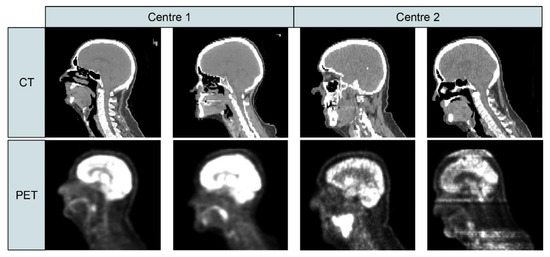

| Armanious et al. [116] | PET, CT images (brain) | Multi-modal dataset | Developed MedGAN architecture which consists of a cascade of UNet blocks to obtain sharper translated images (CasNet) along with Gatys et al.’s [101] style transfer losses. |